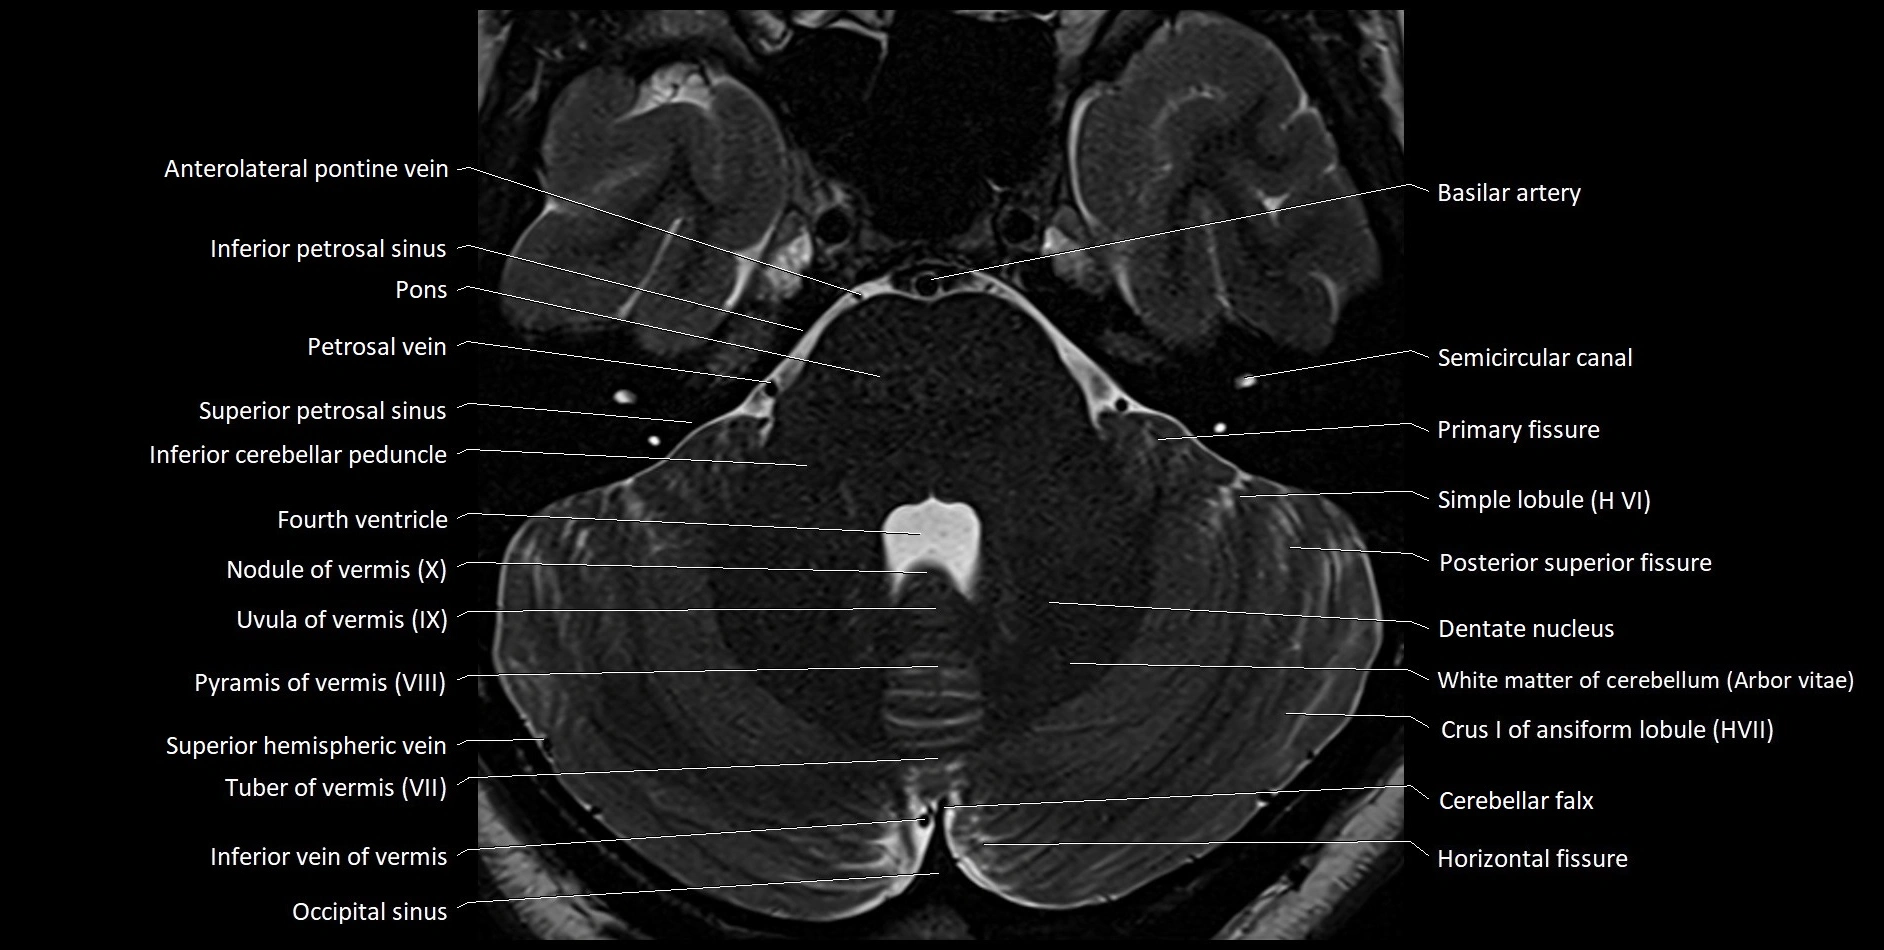

MRI images